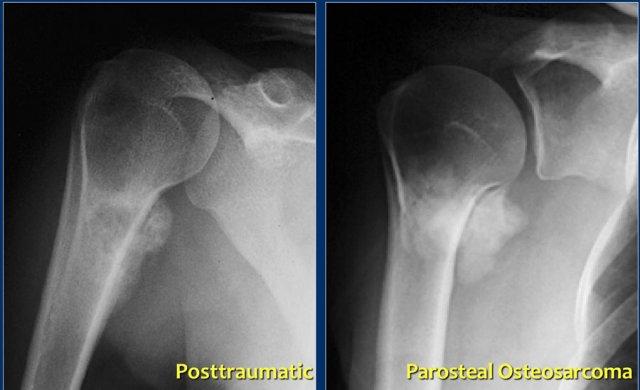

Parosteal osteosarcoma

Ung thư xương cạnh màng xương (Parosteal osteosarcoma) là một loại sarcoma có nguồn gốc từ bề mặt xương.

Khối u phát triển chủ yếu vào các mô mềm xung quanh, nhưng cũng có thể xâm lấn vào tủy xương.

Vị trí thường gặp nhất là ở mặt sau của vùng siêu hành xương đùi xa (meta-diaphysis đầu xa xương đùi).

Sự ossification trong ung thư xương cạnh màng xương (parosteal osteosarcoma) thường trưởng thành hơn ở trung tâm so với ngoại vi. Điều này trái ngược với viêm cơ hóa xương (myositis ossificans), có thể xuất hiện rất gần với xương vỏ, nhưng sự trưởng thành phát triển từ trung tâm ra ngoại vi.

Đây là hình ảnh của một bệnh nhân có khối xơ cứng cạnh vỏ xương ở đầu trên xương cánh tay (trái).

Trường hợp này được xác định là vôi hóa phản ứng thứ phát sau chấn thương.

Lưu ý sự tương đồng với khối u cạnh vỏ xương ở một bệnh nhân khác (bên phải), được chẩn đoán xác định bằng sinh thiết là u xương cạnh màng xương (parosteal osteosarcoma).